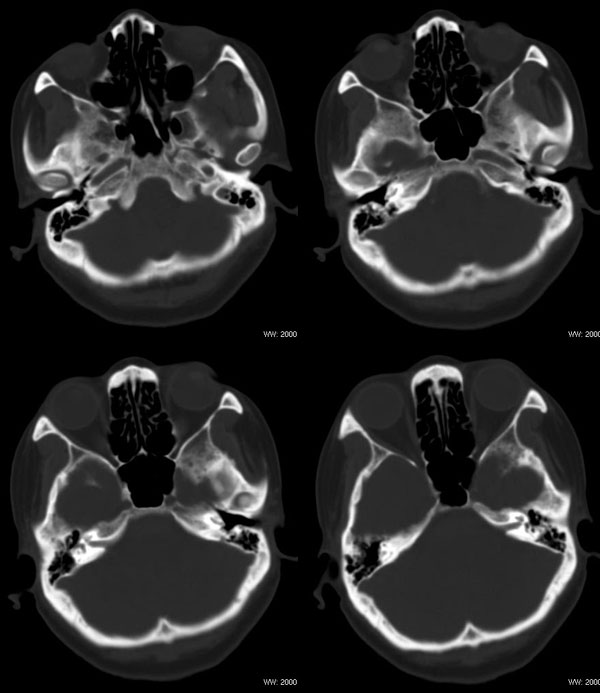

女性,43岁。左腮部肿物5年。体检:(肿物)质中,约5x4x4cm,边界清,固定。

左腮腺肿物,内可见低密度坏死区,增强扫描示肿块明显强化,且呈持续延迟强化,常规考虑腮混合瘤可能性大,但强化表现不太符合,不除外腮腺纤维血管瘤、神经鞘瘤、淋巴瘤及巨淋巴结增生症

左侧腮腺多形性腺瘤可能性大。1、是混合瘤中最常见的良性肿瘤;2、中年女性多见并且时间长症状轻;3、病灶内有低密度坏死区,增强时强化;4、其内有钙化,囊性部分未强化;5、需与囊性淋巴瘤相鉴别。